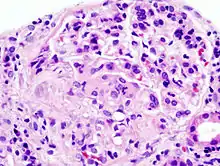

RPGN can be classified into three types, based upon the immunofluorescence patterns:[3]

Type I

Accounting for approximately 3[11]% of RPGN, type I RPGN, also called anti-GBM glomerulonephritis, is characterized by the presence of autoantibodies directed against type IV collagen (specifically, the noncollagenous region of its α3 chain)[2] in the glomerular basement membrane (GBM). Some cases are associated with antibodies directed against the basement membrane of lung alveoli, producing Goodpasture syndrome. The majority of type I disease, however, features anti-GBM antibodies alone; these cases are considered idiopathic.[2]

Type II

Characterized by deposition of immune complexes in glomerular tissues, type II RPGN accounts for 40[12]% of cases. Any immune complex disease—including systemic lupus erythematosus, acute proliferative glomerulonephritis, Henoch–Schönlein purpura, and IgA nephropathy—that involves the glomerulus may progress to RPGN if severe enough.[2]

Type III

Also known as pauci-immune RPGN, type III RPGN accounts for 55% of RPGN and features neither immune complex deposition nor anti-GBM antibodies. Instead, the glomeruli are damaged in an undefined manner, perhaps through the activation of neutrophils in response to ANCA. Type III RPGN may be isolated to the glomerulus (primary, or idiopathic) or associated with a systemic disease (secondary). In most cases of the latter, the systemic disease is an ANCA-associated vasculitis such as granulomatosis with polyangiitis, microscopic polyangiitis or eosinophilic granulomatosis with polyangiitis.[2]